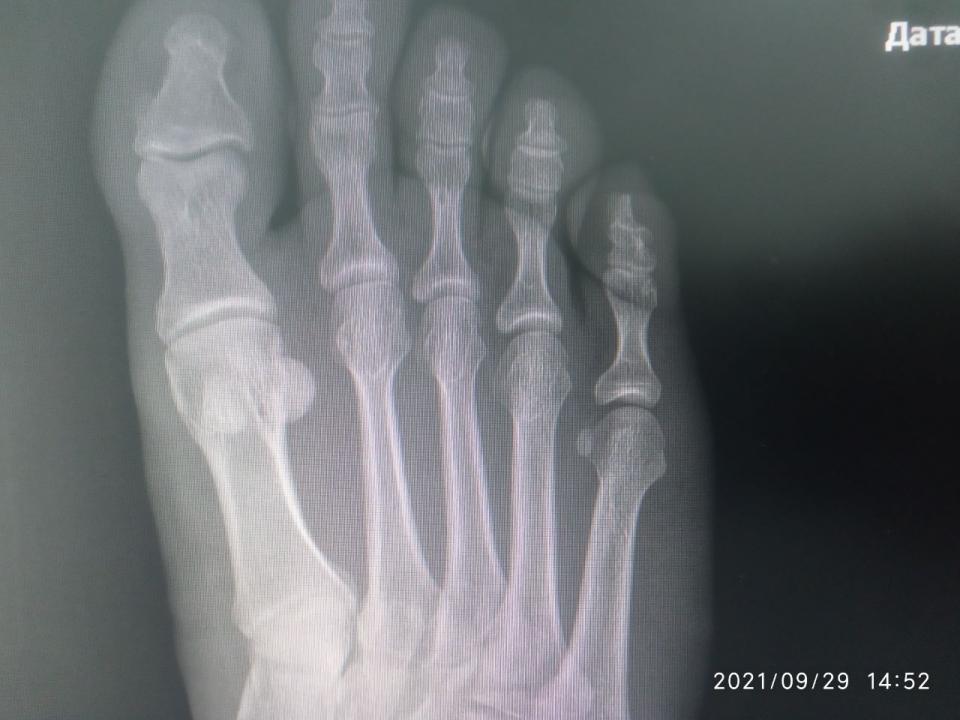

andreyyy Опубликовано 5 октября, 2021 Опубликовано 5 октября, 2021 Драсьте На фоне истощения организма, плохо заживающих ранок, падения иммунитета, что является вообще отдельной темой, не для обсуждения, я неудачно спрыгнул с брусьев. С невысоких. С собственным весом около 70 кг. Просто знаете, бывает, что не достаточно самортизировал и в стопе возникла боль при приземлении. Это было, дай бох памяти, в понедельник прошлой недели. Т.е. 8 дней назад. Сначала боль была несильная. На утро легкая, вполне себе не вызывающая беспокойства. Пошел на работу. От проходной до моего участка работы пешком далеко. Т.е. каждодневный поход н аработу - это всегда большая нагрузка в плане ходьбы. Особенно если опаздываю и иду быстрым шагом. Так я сильно мучился, когдда несколько месяцев не заживали мозоли-волдыри, нратертые обувью. Я купил эластичный бинт и перемотал стопу. По неопытности перетянул сильней необходимого. Идти стало еще больней. Шел через боль, пока боль не стала очень сильной. Остановился, размотался... К вечеру нога разболелась очень сильно. Когда говорю очень, то это буквально. Обезболился, лег спать. Проснулся утром, а боль уже невыносимая. Невозможно ступить на ногу вообще. Больно даже легонько прикоснуться пальцем к коже стопы. Я уссыкаюсь, а не могу идти. Я зову на помощь, мне несут ведро. При этом еще и морозить стало. Я измерил - 39. Напился Парацетамола, Ибупрофена, уколол 3 кубика кетанова и несколько ампул налбуфина. К последнему толерантность и он плохо действует в плане обезболивания. Зависимости нет (была), но толерантность высокая. Одна ампула вообще не дает эффекта. Как-то так. В общем, обезболился и на работу не пошел. Интенсивность боли показалась ненормальной и я поехал на такси в травмпункт. А, сначала получил направлениеп от семейной. Уже попускали лекарства, даже покачивания в такси вызывали сильную пульсирующую боль. Наступил на камушек, так заорал криком... Травмпункт отказался принимать, т.к. они работают только в первые сутки после травмы. Моя семейная такая - всю жизнь меня куда-то направляет, где говорят, что она дура и этот не к ним. Умеет только бубнеть, как сложно ей живется после реформы и как сбоит программа (просто время отклика на клик было чуть дольше чем на хорошем современном ПК, все работает четко, но она бубнит, что вот снова невозможно работать, реформа....). Короче, я там начал ругаться. Я еще нервный последнее время и на транках, которые не работают уже нихера. А шишки потерял ( Добился приема заведующего отделением. Направил на рентген. Я сфотографировал снимки на мониторе и показал ему на телефоне. Он сказал, что все пучком, все в целостности. Прописал покой, холодные компрессы, легкая намотка и капустный лист. Не шутка. А если будет болеть, немид. Если вдруг понадобится больничный, то к семейному. Вот эти "если" умиляли. Я ему же объяснил, что я несколько часов назад не мог до туалета дойти. На следующее утро та же история. В течение дня я всем чем можно обезболиваюсь, соблюдаю режим щадящий, но стоит заснуть и проснуться, как боль невыносимая и невозможно вообще даже с палочкой пройти и пару шагов. Я обнаружил, тчо кетанов не работает совсем. Вчера поставил 3 кетанова и 3 трамадола и боль ушла примерно на 60% Трамадол был последний. Оставалось на всякий случай в заначке 3 кубика. Сегодня ночью я жменями жрал пенталгин, темпалгин, ибупрофен, т.к. не хотел будить никого. Утром докупили кетанов. 2 кубика. Полнейшее отстутствие эффекта. Еще 2. Вообще ноль При этом я абсолютно уверен, что кетанов на мне работает отлично. От сильной зубной или послеоперационной боли 2 кубика снимают боль полностью. Не на долно, но полностью. Никак не связан его эффект с падением эффективности опиоидов. Я озадачен. Я не могу придумать, по какой еще причине он может не работать кроме проблем с кровообращением. С кровообращением, кстати, и правда жопа. Кончики пальцев на ногах потеряли чувтствительность. Но нога-то распухшая, кроме как кончики пальцев всюду чувствительнсоть есть. Уколол 1 налбуфин. Сижу терплаю. Дергает и пульсирует. Усомнившись в правильном ракурсе снимка, я повторно через семейного выбил направление к нашему местному травматологу. Там сделали снимог на пленку. Не знаю, как его выложить. Не могу сфотографировать, чтобы что-то было четко видно. ВЫстоял очередь к травматологу... И хорошо, что с криком "Да пошел ты " выскочил, хлопнув дверью, что штукатурка посыпалась, ибо так психанул, что если бы не выскочил, то перее..л бы его палкой (я с папиной палкой сейчас хожу), Он отказался даже смотреть снимки. К нему только по записи. По направлению нельзя. К тому же он последний день перед отпуском. Последнее он повторил несколько раз. К чему? Сейчас-то он на работе! Я стою с сильной болью, приехал на такси на одолженные деньги, а он давит лыбу и говорит, что он уже почти в отпуске и меня не примит. Ну я начал колоть диклофенак, пить Серротопептидазу. Никаких изменений. Первый рентген (цифровой) Показать Показать Показать Показать Показать Селфи Показать Селфи только что Показать Диагноз поставли "или растяжение или надрыв". Прошу совета. Я сейчас и так очень сильно погружен в решение своих других проблем и не могу много времени выделить на походы по больницам. Ждать и само заживет или что-то идет не так ? КАкие варианты ? Навскидку устрпоит. Вообще чтоб понимать, что МОЖЕТ быть. Чем обезболиваться ? Я не могу вспомнить хороший нецентрального действия преп, который тоже хорошо помогает в плане обезболивания (чуть ли не на уровне кетаролака). Что из сильного ненаркотического ? буду пробовать все.